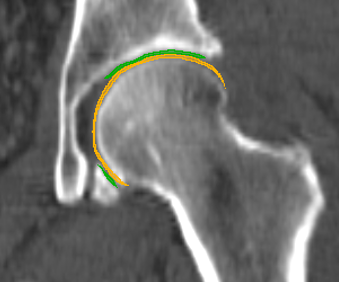

where 𝐁𝐂(𝐟)𝐁𝐂𝐟\mathbf{BC}(\mathbf{f}) is the barycenter of face 𝐟𝐟\mathbf{f}. We refer to this subset of faces and vertices as CDsuperscriptsubscript𝐶𝐷\mathcal{F}_{C}^{D} and its corresponding vertices as 𝒱CDsuperscriptsubscript𝒱𝐶𝐷\mathcal{V}_{C}^{D}. The distance filter parameter, δ𝛿\delta, should be based on the gap between the femur and pelvis, as it determines the initial approximation quality. The femur’s initial estimate must be located above the anatomical line of the femoral head (Fig. 1(a)). Otherwise, we do not enforce any restrictions on δ𝛿\delta. To provide additional robustness to the initial guess, we trim the outer boundary by removing layers from its outer rim and discarding faces with two boundary edges. The trimming helps ensure the initial estimate does not become too large, and in particular, makes it simpler to avoid selecting triangles crossing the natural ridges of the bone.

Figure 1: Computing initial bone-cartilage interface for femur ((a)-(c)) and pelvis ((d)-(f)). Initially, in (a) and (d), triangles on the surface of the femur and pelvis are selected based on the distance to the opposite bone (Eq. (1)). Afterwards, in (b) and (e), the initial sets are trimmed to remove triangles that only have one neighbour. The trimmed region can be seen in red on top of the initial guess in yellow. Finally, we select the biggest cluster of triangles as our initial estimate of the bone-attached region for both femur and pelvis ((c) and (f)).

The pelvis is more sensitive to the distance filtering parameter than the femur, as most of the cartilage exists in a plateau in the pelvic socket. This implies the bone-attached region does not require any additional refining, as the initial estimate accurately aligns with anatomical lines (Fig. 1(d)). The distance filtering step typically results in fragmented bone-attached regions, and before we proceed, we discard all but the largest of these regions (Fig. 1(f)). We can safely discard the smaller regions, as we grow the cartilage during the next step of our algorithm to incorporate all triangles within an area of similar curvature.